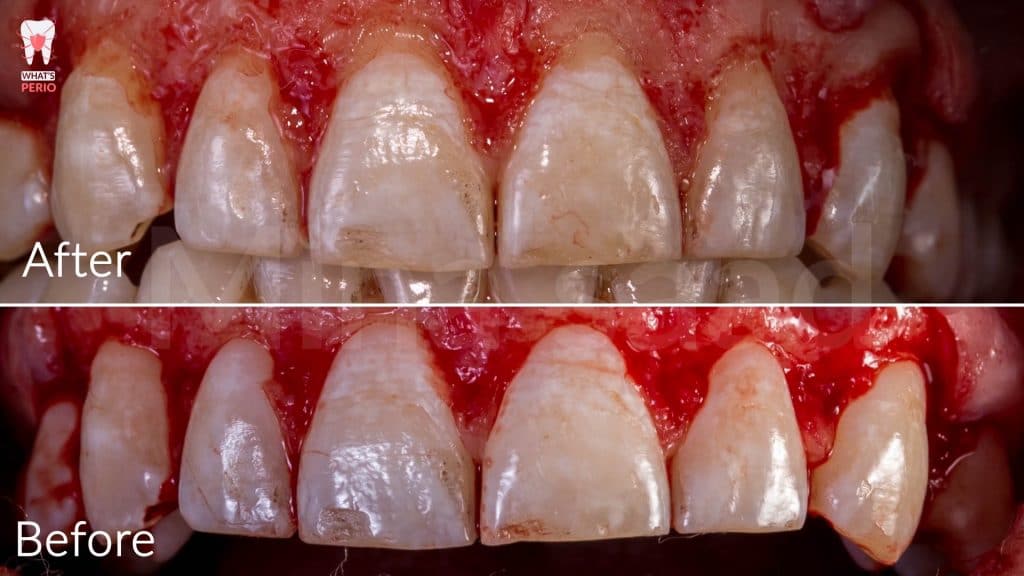

-External bevel gingivectomy was made while the guide in place.

-Internal bevel incision was made “envelope flap” to expose underlying labial plate of bone.

-Care was taken during flap elevation to make a split-thickness incision under each papilla to preserve underlying periosteum interdentally as there is no need to expose interdental bone.

-The guide was placed again over labial plate of bone & it was noted that its apical level is higher than alveolar crest level.” Which confirms that the design on CBCT was accurate”

-Ostectomy was made using a rose head diamond stone then the guide was put in place again & it was observed that the apical level & the alveolar crest is at the same level now.

-A periodontal probe was placed between CEJ & alveolar crest to measure the distance which was 2mm. “ensuring that the digital guide is accurate”

-Osteoplasty wass performed to reshape the prominent canine eminence to be in harmony with the left one & in general the labial plate of bone was shaped & any sharp angles resulting from ostectomy procedure were removed for better adaptation of the flap ensuring nice healing results.

-The flap was sutured using single sling sutures. “4/0 Vicryl sutures” “resorbable”